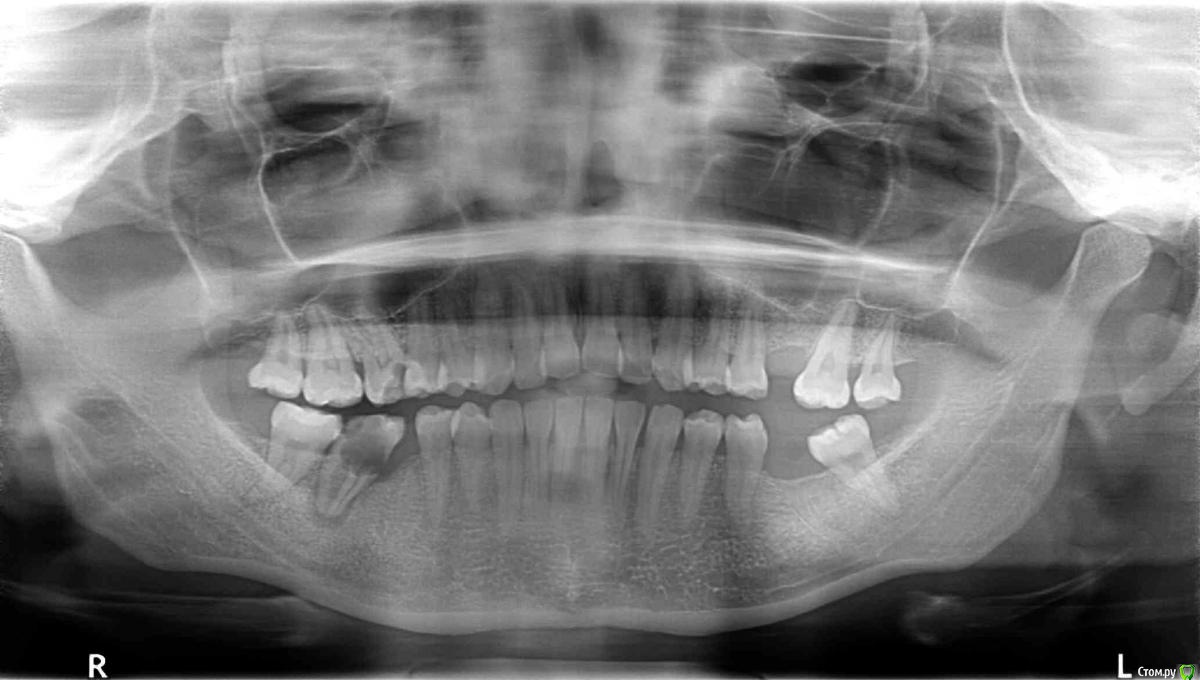

Здраствуйте.меня зовут Ольга.мне 26 лет.брекеты ношу 2 г и 7 м.Подскажите мне пожалуйста что можно сделать в моей ситуации.У меня дистальный прикус.был 11 мм.Не было одного шестого зуба на в.ч с одной стороны.и под удаление был уже второй.поэтому врач перетенул 5,4 и все остальные зубы на место 6.сагитальная щель осталась 5 мм.но врач сказал что сделать ничего со мной нельзя тут только операция...чего я очень сильно боюсь.и предложила сделать наклон нижних передних зубов чтоб хоть как то было смыкание...Стабилен ли будет такой вариант или что можно сделать?!пожалуйста подскажите.Снимки и фото прилогаю.снимки сделаны перед брекет системой.почему то последние фото загрузились перевёрнутыми

НЕТ. наклонять нижние резцы до смыкания  при щели в 5 мм нельзя !

в идеале - выравнивание окклюзионной плоскости (у Вас  боковой отдел на взлет идет)  и постановка нижней челюсти в правильное положение (либо аппараты по типу Гербста либо операция - решается при расчете снимков, либо оставлять как есть)